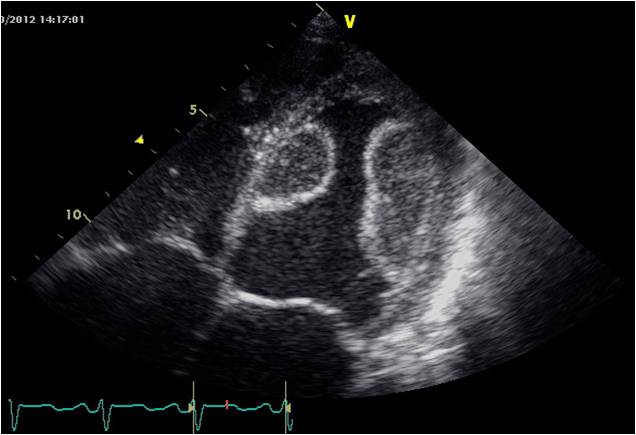

ベストインパクトイメージング賞

氏 名 : 永沼 晃和

所 属 : JA北海道厚生連 遠軽厚生病院

診断名: 『左室内血栓』

装 置 : GE Vivid 7, M4Sプローブ

対 象 : 60歳代男性

コメント: 大きな乳頭筋?いえいえ新鮮血栓です。観察中もプルプル揺れていて、

今にも中身が飛び出しそうでした! |